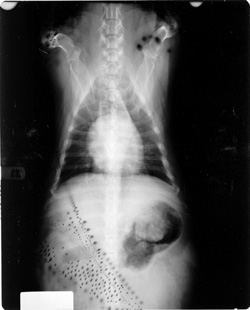

Static causes black branching artifact on the film due to exposure of the film to the elecrical spark of the static discharge.